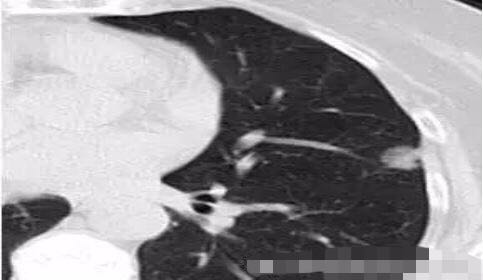

病例2

随访3年,GGO直径基本没有变化

2013年12月

2014年7月

2015年5月

2016年10月